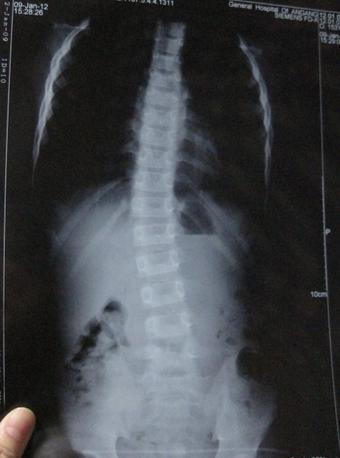

(图:X线片显示季同学脊柱已经成中度弯曲)

2017年7月,刚刚拿到大学录取通知书的他却出现下腰背部疼痛现象,特别是一旦遇到温度突然下降的时候,双侧髋关节疼痛为重,夜间睡觉腰背发僵,翻身困难,到当地医院检查;X线示:双侧髋关节间隙狭窄,HLA-B27(+),血沉43mm/h,诊断为:强直性脊柱炎,因为着急到校报到,未坚持系统用药治疗,病情逐渐加重,至行走困难。

体格检查:“4”字试验检查,臀部出现疼痛,屈腿侧存在骶髂关节疼痛;枕墙实验,枕骨结节与墙之间的水平距离开始变大,脊柱出现中度弯曲变形。

CT检查显示:脊柱出现韧带钙化、脊柱出现初期“竹节样”改变,以及椎小关节和脊柱生理曲度改变。